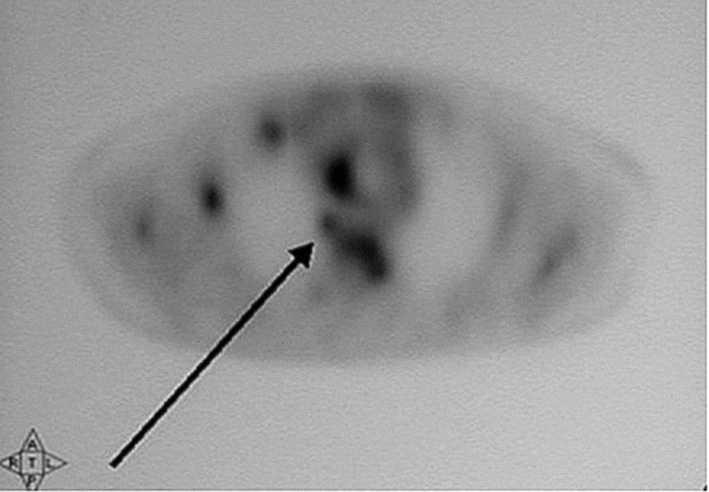

Un varón de 76 años acudió al hospital por fiebre y disfonía. Quince años antes había sido intervenido quirúrgicamente, tras sufrir la rotura de un aneurisma de la aorta abdominal, realizándose una endoaneurismorrafia y un injerto aorto-bifemoral. Dos meses antes había ingresado por presentar una miositis abscesificada en muslo derecho que precisó drenaje quirúrgico. La exploración era anodina a excepción de las secuelas de las intervenciones quirúrgicas previas y la disfonía. Entre los datos analíticos destacaba la existencia de leucocitosis (11.600/ml) con neutrofilia, anemia (Hb: 10 g/dl) normocítica normocrómica, elevación de la velocidad de sedimentación globular (VSG) (60 mm/ primera hora) y aumento de la lacticodeshidrogenasa (LDH) (604 UI/l). El urinocultivo fue negativo, mientras que en los hemocultivos creció una Escherichia coli. En el examen otorrinolaringológico se observó la existencia de una parálisis de la cuerda vocal derecha. La radiografía de tórax mostraba signos de hipertensión arterial pulmonar y atrapamiento aéreo. La tomografía computarizada (TC) de cuello y tórax puso de manifiesto la existencia de un nódulo de 1,3 cm de diámetro en lóbulo superior derecho (LSD), que hacía contacto con la pleura de la pared torácica posterior. En la gammagrafía ósea con 99mTc se observaron varios focos hipercaptadores en parrilla costal izquierda y esternón, así como un patrón heterogéneo irregular en la columna vertebral. La tomografía por emisión de positrones (PET/ TC) reveló la existencia de captación sugestiva de malignidad en el nódulo pulmonar del LSD (fig. 1), en los ganglios mediastínicos, glándula suprarrenal izquierda y parénquima hepático, así como múltiples focos hipercaptantes en el esqueleto compatibles con una diseminación ósea metastásica (figs. 2, 3 y 4). En las citologías de esputo y en el aspirado bronquial se observaron células atípicas sugestivas de carcinoma no microcítico (carcinoma indiferenciado).

Fig. 1. Corte axial de la tomografía por emisión de positrones con fluorodesoxiglucosa (PET-FDG) (A) y de la PET/ tomografía computarizada (TC) (B) que muestra varios focos hipercaptantes que corresponden al nódulo pulmonar solitario del lóbulo superior derecho (flecha), ganglios mediastínicos y cuerpo vertebral.